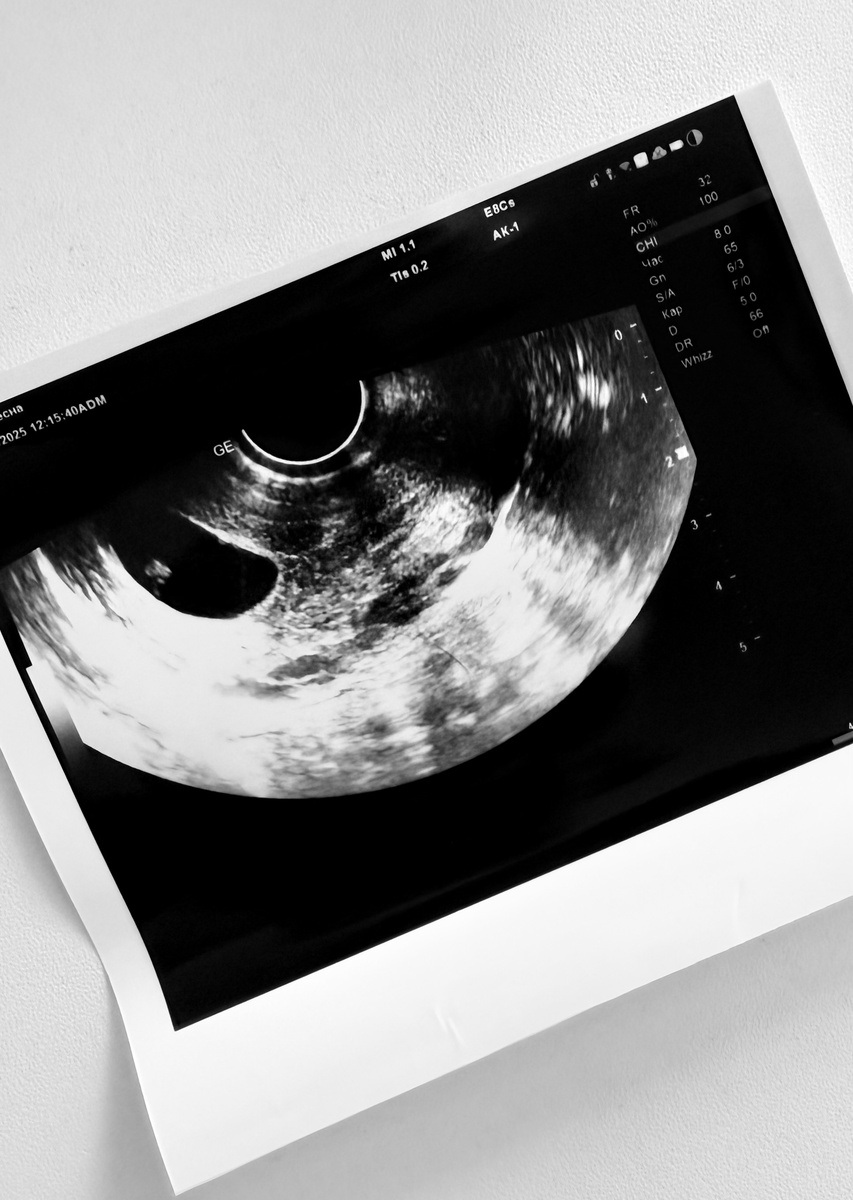

Все УЗИ проводились абдоминальным датчиком.

Необходимо трансвагинальное УЗИ

Несколько раз пытаюсь прослушать сердцебиение. Хотя по картинке уже вижу, что нет никакого мерцания.

К сожалению, последнее УЗИ оказалось верным.

Да, там действительно неразвивающаяся беременность.

Замерла она точно не два дня назад. По менструации срок должен быть уже 10 недель, а УЗИ показало 6-7. Уже началось разрушение тканей, эмбрион уже был неполноценным.